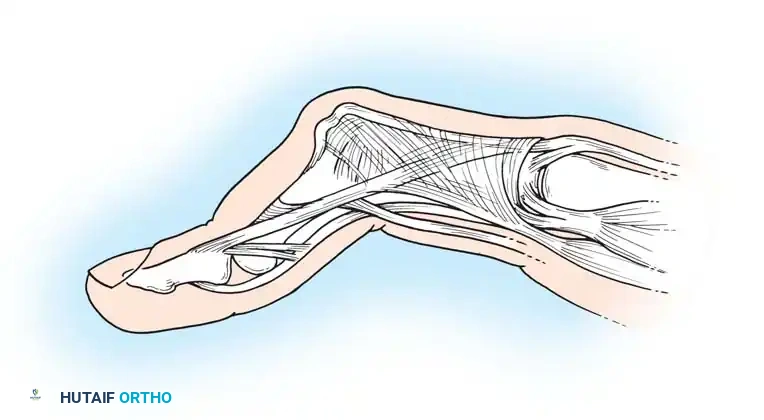

The swan-neck deformity is defined by a primary hyperextension posture of the PIP joint and a flexion posture of the DIP joint, often accompanied by flexion of the MCP joint. It is driven by profound muscle imbalance and capsular attenuation.

- DIP Joint Origin: The deformity may begin as a mallet finger due to attenuation or disruption of the terminal extensor tendon at the DIP joint. This leads to secondary overpull of the central slip, causing hyperextension of a lax PIP joint.

- PIP Joint Origin: Synovitis of the PIP joint causes herniation of the volar capsule and attenuation of the volar plate. This allows the lateral bands and central tendon to subluxate dorsally. Eventually, the lateral bands adhere in a fixed dorsal position, preventing them from sliding volarly over the condyles during PIP flexion.

Beckenbaugh observed that flexor tenosynovitis results in ineffective volar support by the flexor digitorum superficialis (FDS) tendon, acting as a primary catalyst for swan-neck deformity. Adherence of the FDS tendon prevents it from stabilizing the PIP joint against hyperextension. The unopposed overpull of the central tendon, combined with PIP synovitis, stretches the volar plate, locking the joint in hyperextension.

To counteract this, Beckenbaugh advocated creating a volar tenodesis across the PIP joint using one slip of the FDS tendon.